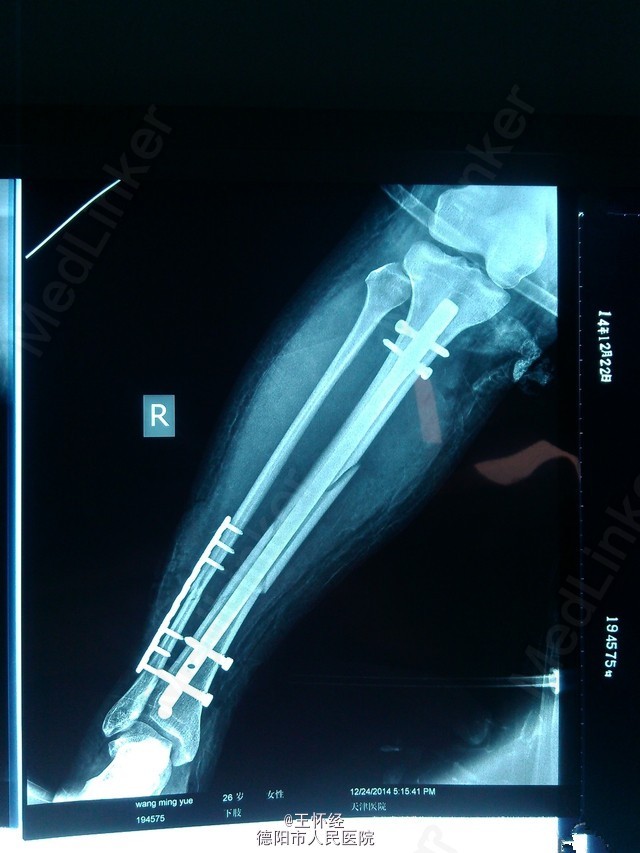

胫腓骨骨折闭合复位

患者女性,26岁,3日前滑雪致右胫腓骨粉碎性骨折,待时机适合时行手术治疗。